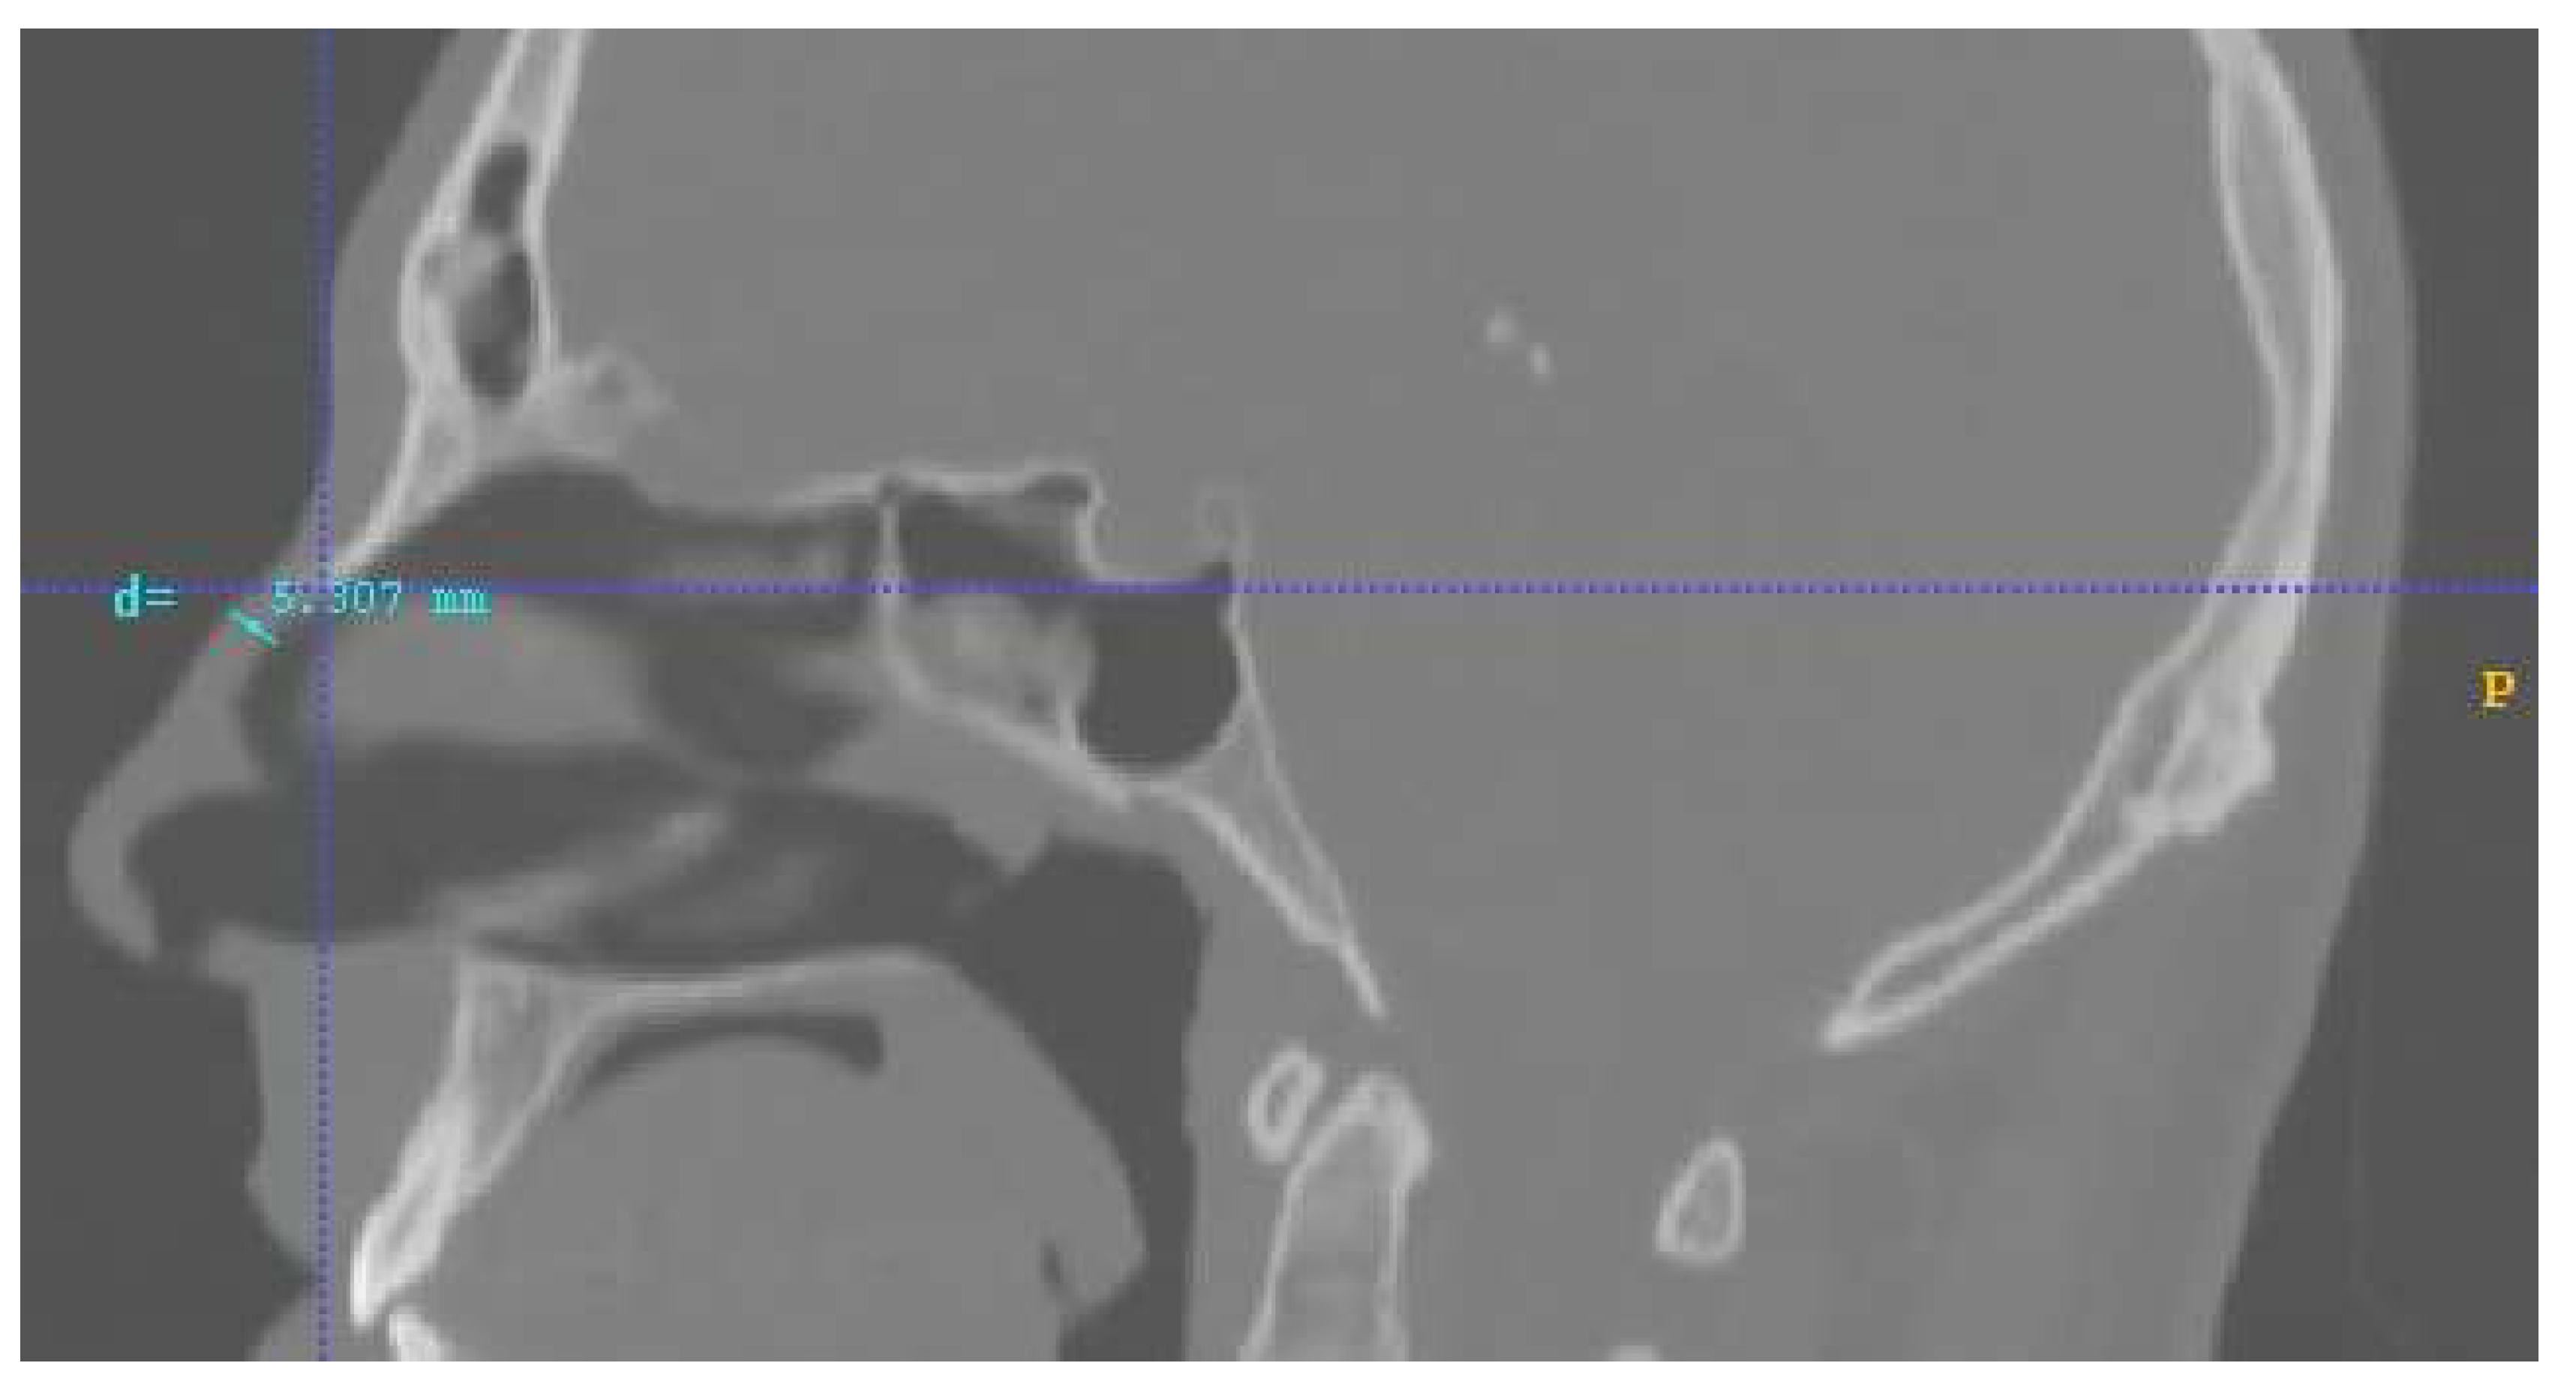

2.1. The Nose and Nasopharynx Model